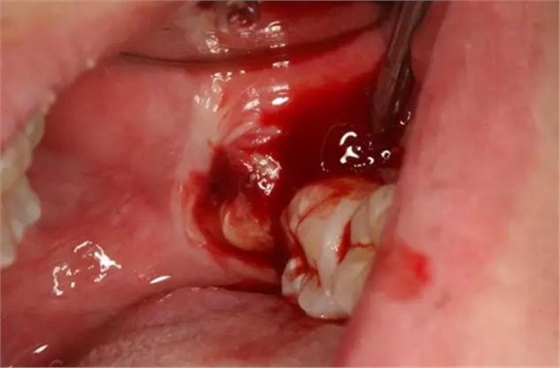

圖6.患者年輕、骨質(zhì)比較軟。牙挺放置在38牙根近中,先用推力豎直38牙冠、然后用挺力直接挺出38

圖7.炎癥期拔牙出血較多、放置止血海綿一塊,壓迫止血半小時